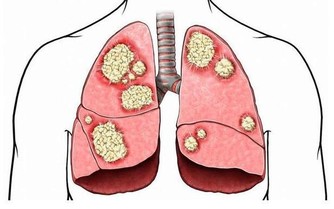

還長了顆水泡,且經常散發出膿液,後來確診王先生罹患了「舌癌」。

舌癌是第一大口腔癌,也被視為「全球第六高發癌症」,

多好發於抽菸者、牙齒不好者、飲食過辣過燙者。